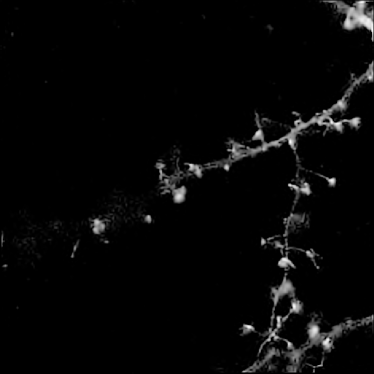

Finally, we applied our algorithm on a real confocal microscopy image of neurons. Fig. 4(a) depicts the observed image222Courtesy of the GIP Cycéron, Caen France. using the GFP fluorescent protein. Fig. 4(b) shows the restored image using our algorithm with the orthogonal wavelets. The images are shown in log-scale for visual purposes. We can notice that the background has been cleaned and some structures have reappeared. The spines are well restored and part of the dendritic tree is reconstructed, however some information can be lost (see tiny holes). This can be improved using more relevant transforms.

Refer to caption Refer to caption

(a) (b)

Fig. 4: Deconvolution of a real neuron. (a) Original noisy, (b) Restored with our algorithm